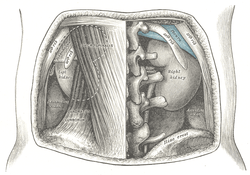

Overview of Ilium as largest bone of the pelvis.

The crest of the ilium (or iliac crest) is the superior border of the wing of ilium and the superolateral margin of the greater pelvis.

Structure

The iliac crest stretches posteriorly from the anterior superior iliac spine (ASIS) to the posterior superior iliac spine (PSIS). Behind the ASIS, it divides into an outer and inner lip separated by the intermediate zone. The outer lip bulges laterally into the iliac tubercle. [1] Palpable in its entire length, the crest is convex superiorly but is sinuously curved, being concave inward in front, concave outward behind. [2]

It is thinner at the center than at the extremities.

To the external lip are attached the Tensor fasciae latae, Obliquus externus abdominis, and Latissimus dorsi, and along its whole length the fascia lata; to the intermediate line, the Obliquus internus abdominis. To the internal lip, the iliac fascia, the Transversus abdominis, Quadratus lumborum, Sacrospinalis, and Iliacus.